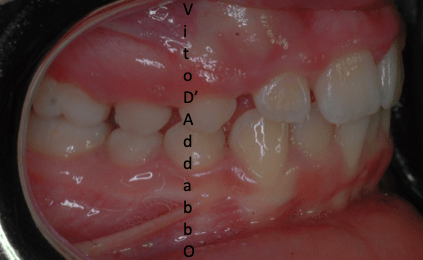

In alcune malocclusioni i denti superiori non coprono adeguatamente quelli inferiori con la presenza in alcuni casi di una beanza fra le due arcate. Questo può essere dovuto ad abitudini viziate come il succhiamento del dito, una deglutizione scorretta, una postura della lingua alterata o un problema scheletrico. In questo esempio il problema è associato ad una terza classe scheletrica.

prima